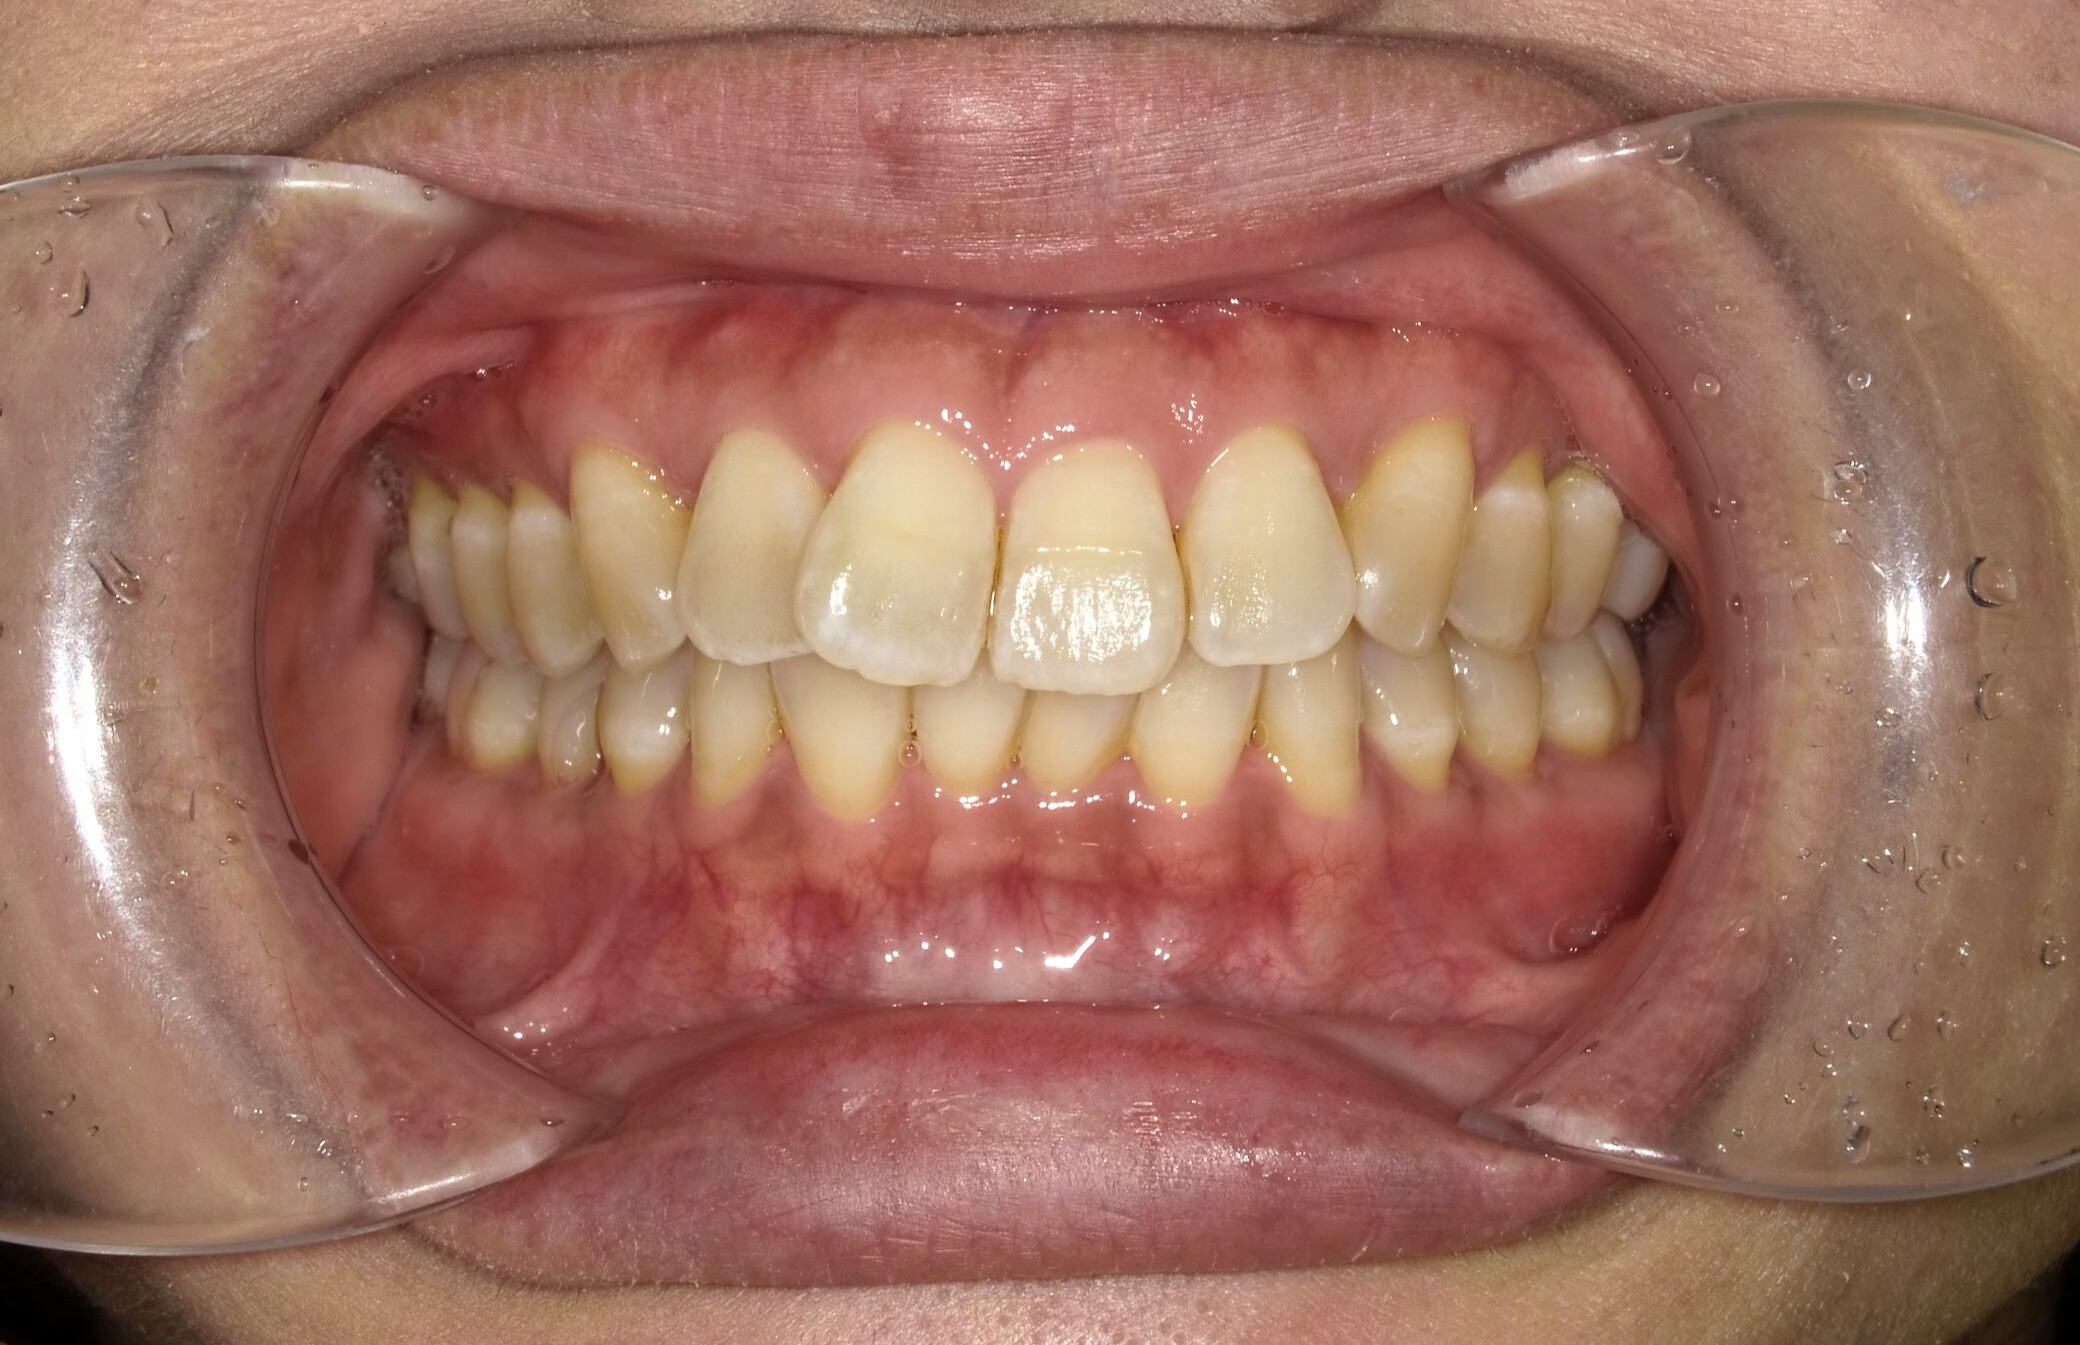

Before

5ヶ月経過の口腔内写真比較